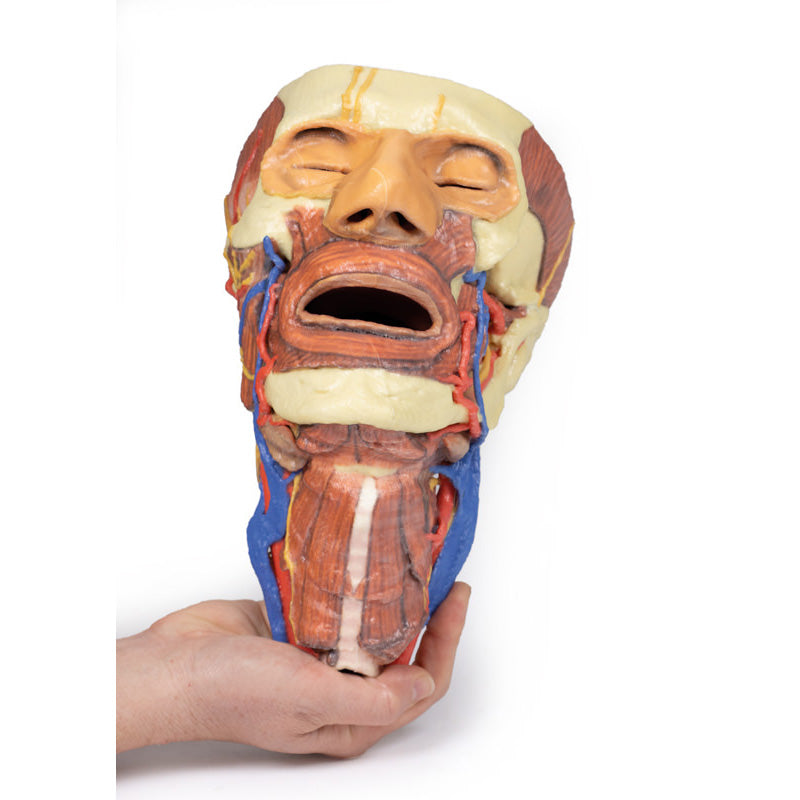

Viewed from the anterior aspect the face has been dissected to display some of the facial muscles around the mouth (buccinator [on the left], orbicularis oris and zygomaticus major). On the left side of the infratemporal fossa has been open to expose the medial and lateral pterygoids.

The lateral pterygoid is divided to show the mandibular division of the trigeminal nerve dividing into the lingual nerve and the inferior alveolar branch. Also on the left side the branches of the ophthalmic division of the trigeminal that supply the skin above the eyebrows and scalp (supraorbital [left only] and supratrochlear nerves [both sides]) are dissected. The submandibular gland is clearly visible below the mandible on both sides as are the facial arteries and veins as they course over the mandible.

The neck: The musculoskeletal portion of the neck have been removed to display the pharynx posteriorly, the larynx anteriorly, and the neurovascular bundles laterally. The suprahyoid and infrahyoid muscles can be seen on the neck, as well as the cricothyroid muscle.

When looking up the length of the trachea from below, the vocal folds are visible. The hypoglossal nerve can be seen winding around the lateral surface of the external carotid artery and the external branch of superior laryngeal nerve is seen descending in the neck. The internal jugular vein, the common carotid artery and its bifurcation into external and internal carotid arteries are clearly seen on both left and right. The vagus nerve in the carotid sheath is also visible. The ansa cervicalis is visible emerging below the digastric muscle and descending on the surface of the internal jugular vein. The internal branch of the superior laryngeal nerve can be seen below the superior thyroid artery on the left. The superior thyroid artery branching from the external carotid artery is seen descending in the anterior neck. The internal branch of the superior laryngeal artery is visible on the left piercing the thyrohyoid membrane above the inferior constrictor where this muscle is attached to the hyoid bone.

This 3D print specimen preserves a series of features of the head and visceral column of the neck:The face: On the right side of the head the parotid gland has been removed to reveal the facial nerve and all its branches (temporal, zygomatic, buccal, marginal mandibular and cervical) and demonstrate the spatial relations of structures embedded in the gland from superficial to deep (facial nerve, retromandibular vein, external carotid artery). In the surrounding region the temporalis, masseter and posterior belly of digastric are exposed, as are and the facial artery, transverse facial artery and superficial temporal artery. The facial vein and transverse facial vein are clearly visible uniting to form the common facial vein which is joined by the retromandibular vein to form the external jugular vein.

Viewed from the anterior aspect the face has been dissected to display some of the facial muscles around the mouth (buccinator [on the left], orbicularis oris and zygomaticus major). On the left side of the infratemporal fossa has been open to expose the medial and lateral pterygoids.

The lateral pterygoid is divided to show the mandibular division of the trigeminal nerve dividing into the lingual nerve and the inferior alveolar branch. Also on the left side the branches of the ophthalmic division of the trigeminal that supply the skin above the eyebrows and scalp (supraorbital [left only] and supratrochlear nerves [both sides]) are dissected. The submandibular gland is clearly visible below the mandible on both sides as are the facial arteries and veins as they course over the mandible.

The neck: The musculoskeletal portion of the neck have been removed to display the pharynx posteriorly, the larynx anteriorly, and the neurovascular bundles laterally. The suprahyoid and infrahyoid muscles can be seen on the neck, as well as the cricothyroid muscle.

When looking up the length of the trachea from below, the vocal folds are visible. The hypoglossal nerve can be seen winding around the lateral surface of the external carotid artery and the external branch of superior laryngeal nerve is seen descending in the neck. The internal jugular vein, the common carotid artery and its bifurcation into external and internal carotid arteries are clearly seen on both left and right. The vagus nerve in the carotid sheath is also visible. The ansa cervicalis is visible emerging below the digastric muscle and descending on the surface of the internal jugular vein. The internal branch of the superior laryngeal nerve can be seen below the superior thyroid artery on the left. The superior thyroid artery branching from the external carotid artery is seen descending in the anterior neck. The internal branch of the superior laryngeal artery is visible on the left piercing the thyrohyoid membrane above the inferior constrictor where this muscle is attached to the hyoid bone.